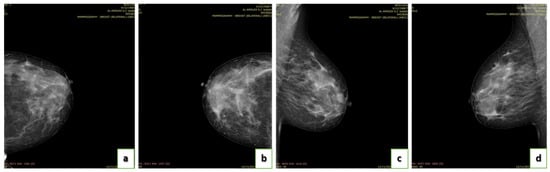

4.3. Data Acquisition

4.4. Breast Density

- A (0–25%): Almost entirely fatty indicates that the breasts are almost entirely composed of fat. One out of ten women has this result.

- B (25–50%): Scattered areas of fibroglandular density indicate some scattered areas of density, but most of the breast tissue is non-dense. Four out of ten women have this result.

- C (50–75%): Heterogeneously dense indicates that there are some areas of non-dense tissue but that most of the breast tissue is dense. Four out of ten women have this result.

- D (75–100%): Extremely dense indicates that nearly all breast tissue is dense. One out of each women has this result.